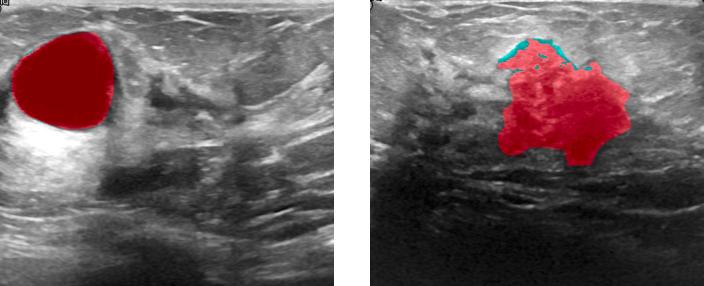

It consists of 778 ultrasound scan images with their corresponding masks: 435 images containing benign breast tumors, 210 images of malignant breast tumors, and 133 normal breast images. The bounding boxes are automatically extracted from the mask. We added an offset of 10 pixels to each bounding box width and height to capture appropriately the contrast between the edges of the tumor and the normal tissue of the breast. We augmented the dataset 6 times through basic and deep learning-based data augmentation techniques. The figures below show different ultrasound scan images with their corresponding mask (red area). The dataset was split into a train set (80% of the dataset), a validation set (10% of the dataset), and a test set (10% of the dataset). we choose to perform cross-validation to mitigate the effect of outliers: We split the train-validation set into 9 folds based on their classes (benign, malignant, or normal). Each time 8 folds are used as a train set and the remaining folder is used for validation.

Benign tumors[43] share a number of features on ultrasound that indicate their benignity. In particular a round or oval shape , a large axis parallel to the skin, circumscribed margins or gently curving smooth lobulations , hyperechoic tissue in the case of solid tumors and anechoic content in the case of cysts and acoustic shadows in the edge. In contrast, malignant tumors[43] show specific features on ultrasound including, irregular shape with microlobulations or spiculations, a large axis that is not parallel to the skin, poorly defined margins, hypoechoic nodule or hetergenous echostructure and acoustic posterior shadowing. a visual analysis of the figures 4 and 5 prove that our model is able to capture the most relevant features we have already described.